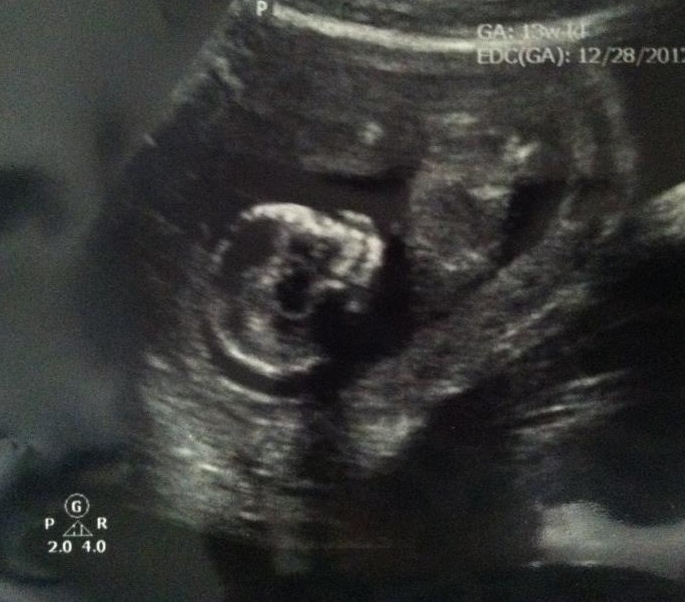

This is for my friend, this is from her 15 week scan, best pic she has. Obviously you can't see the nub but do you have any skull guesses? Thanks!

I think girl but I don't have a great track record on skull guesses - my daughter had a very flat face in comparison to my sons and that baby has a flat face so that's why i would guess that - I wonder if you might be able to see pics of any other kiddos she has to compare??